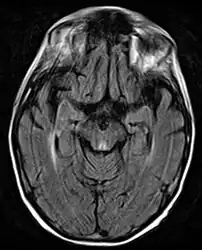

Axial MRI B=1000 DWI image showing hyperintense signal indicative of restricted diffusion in the mesial dorsal thalami. -